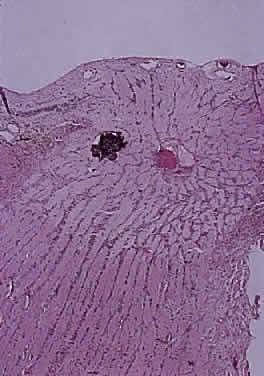

Hypoplasia of the optic nerve is also rare but is more common than aplasia (Figs. 13 and 14). It represents one of the most important developmental abnormalities of the eye and is increasingly recognized as a significant cause of visual deficit in children. Congenital nerve hypoplasia is a nonprogressive condition associated with a reduction in the number of retinal ganglion cells and axons. It may be either unilateral or more commonly bilateral and may involve the entire nerve or be segmental. Although a hypoplastic optic nerve is usually idiopathic, an increased incidence has been noted in the offspring of diabetic mothers and with the maternal use of phenytoin, quinine and, alcohol. Rare reports of an inherited disorder may be found in the literature. Although it may be an isolated abnormality, the hypoplasia is frequently associated with other anomalies—both ocular and nonocular. Additional ocular abnormalities include microphthalmos and congenital nonattachment of the retina. The most common nonocular abnormalities associated with congenital optic nerve hypoplasia include midline CNS structural defects, including septo-optic dysplasia of the septum and ectropia of the posterior pituitary, producing diabetes insipidus.

Fig. 13. Hypoplasia of optic nerve (hematoxylin and eosin staining). Note lack of formation of optic disc tissue.

In optic nerve hypoplasia, the optic disc appears gray and is about half its normal size but retinal vessels are present because the optic stalk is invaginated by mesoderm. The optic foramen is also small. Clinically, there may be strabismus, nystagmus, and decreased visual acuity. Severe cerebral abnormalities may be present but the hypoplastic nerve may be the sole abnormality.